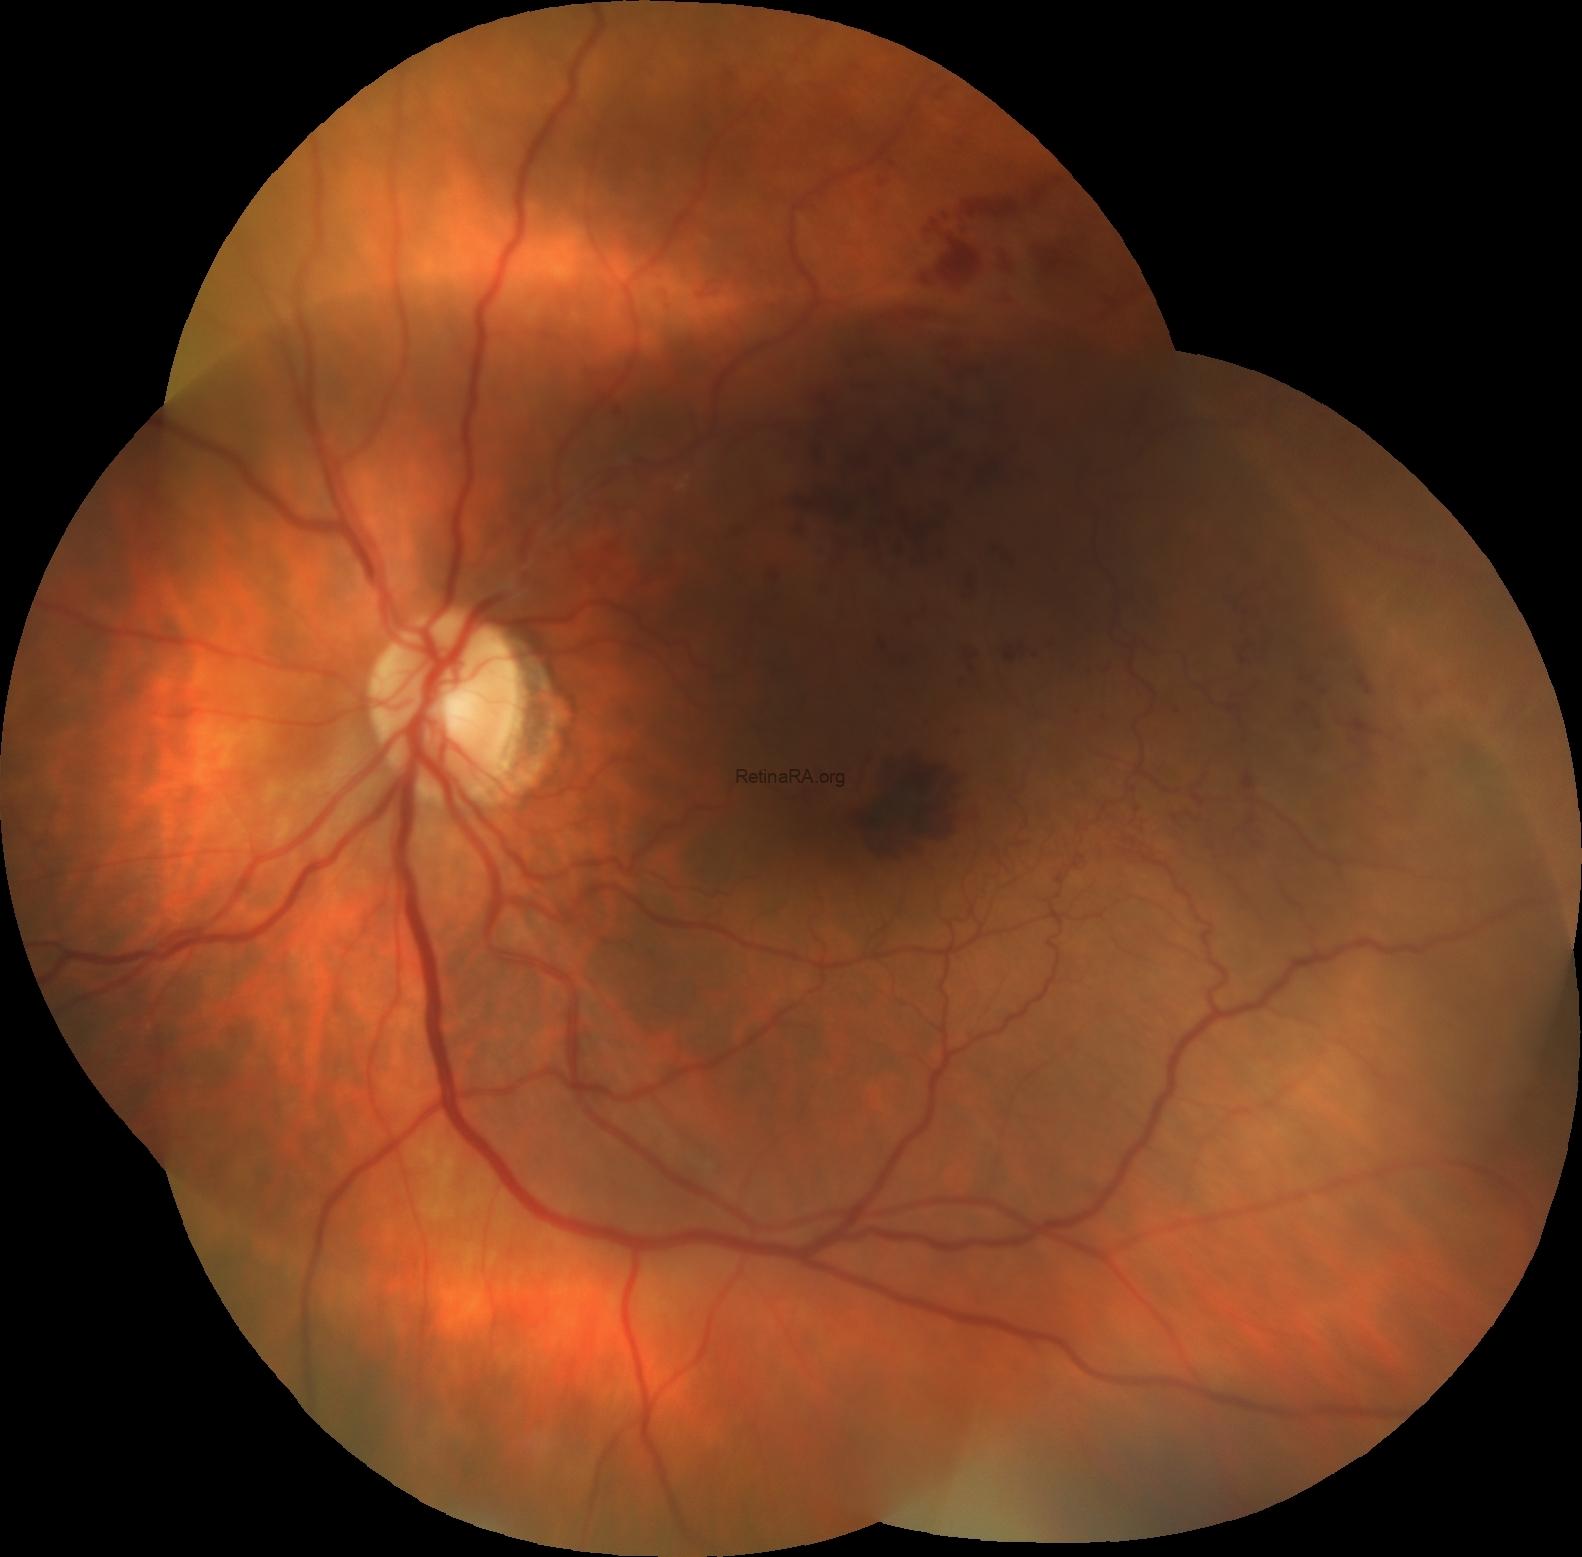

Fundus examination of the left eye revealed feathery (tufy) hemorrhages in the temporal foveal region, accompanied by dot-blot hemorrhages and prominent collateral vessels in the superior and temporal macula.

Fluorescein angiography revealed areas of retinal ischemia and confirmed the presence of collateral vessels in the superior and temporal macula.